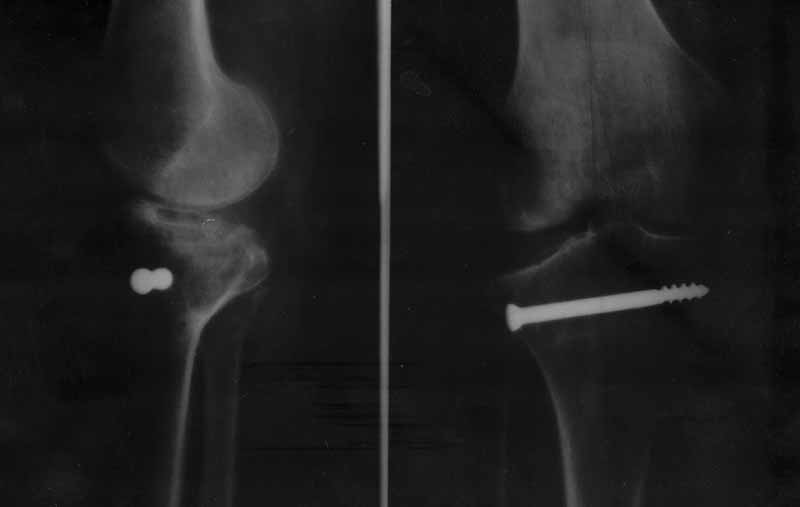

Вчера прооперировал 56 летнюю коллегу, кардиолога с вальгусным, нестабильным коленом. 7 месяцев назад в одной из больниц ввинтили винт, не пытаясь поднять плато. Боли, вальгусная установка привели к нам. До операции было разъяснено, что вариант элевации латерального плато может быть невозможен и будет сделана варизующая остеотомия.Час искал заросший винт, слегка поднял плато остеотомом, но все же выполнил высокую варизующую остеотомию, стабильно скрепил АО L- образной пластиной. Сустав вполне стабилен. Сегодня коллега устроила истерику, Вы мне слепили кривую ногу, на другой ноге у нее 9гр вальгуса, на оперированной 6 гр варуса. Слова до нее не доходят,сижу в раздумьях-может и не стоило браться, чужое... разгребать В анамнезе 5 лет назад мастэктомия, химия, лучевая, остеопороз, фон тот еще.. Прилагаю дооперационный снимок.

если связочный аппарат стабилизирует сустав и фиксация стабильна, то все нормально. Лично мне кажется, что в данном случае лучше недокорригировать (на 3 градуса), чем создать механический ноль. Отправляйте п/о снимки.